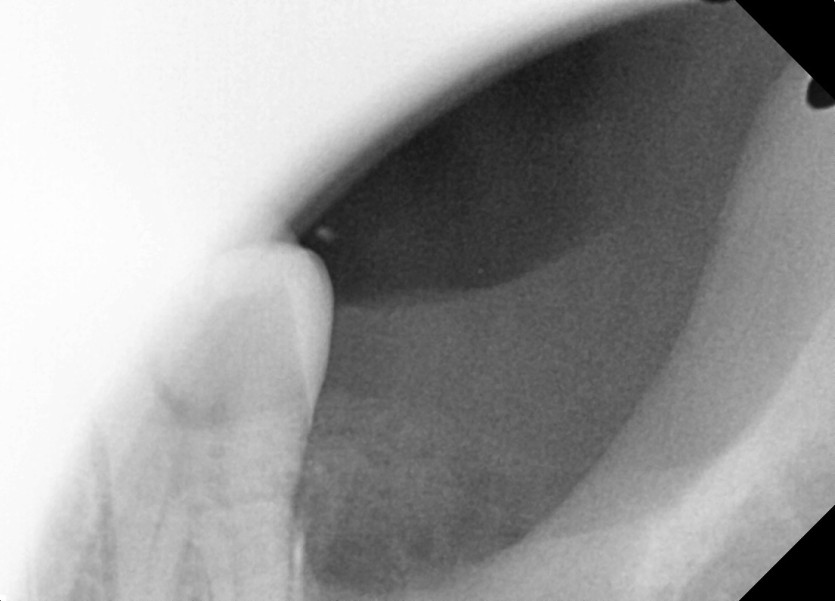

#38 사랑니 발치

구강 외과 전문의가 당일 발치했습니다.